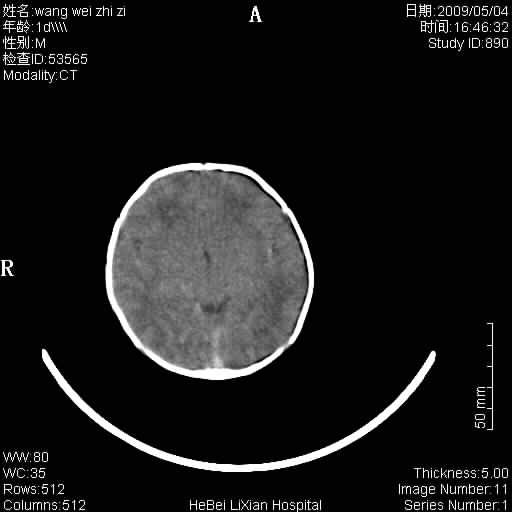

局部5毫米薄层扫描

考虑 缺氧缺血性脑病伴蛛网膜下腔出血,可疑左侧硬膜下积液

支持,至少双侧外侧裂比较像,缺血缺性脑病有待进一步考证,建议治疗后1到2周复查